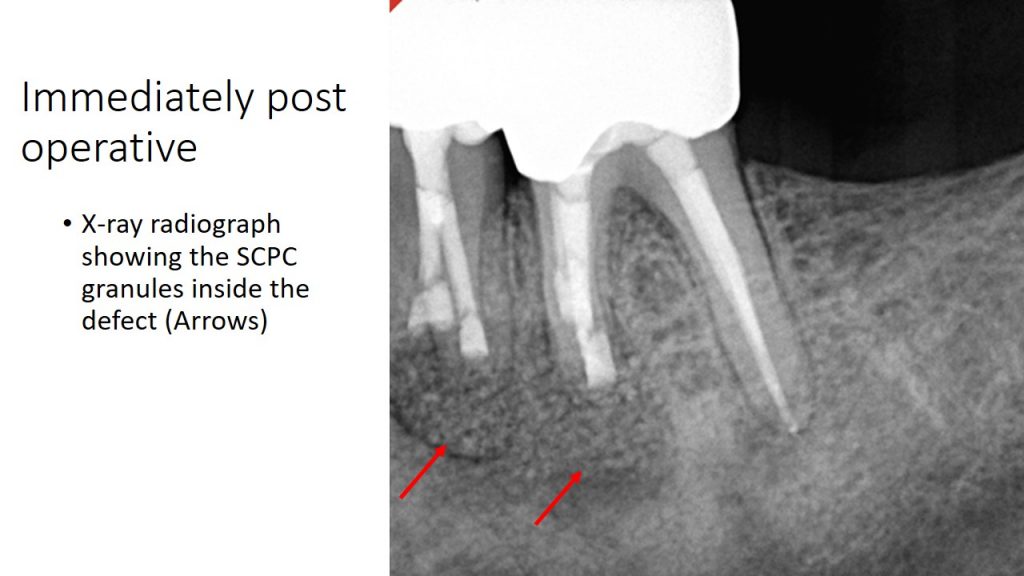

From shefabone.com

EndodonticsCase2 Shefa Bone Endodontic Cases Pridase 2024 guidelines for reporting diagnostic accuracy studies in endodontics: A leading dental journal, endodontic practice us is your publication for endodontic continuing education, endodontic case studies, and more. Stephen buchanan discusses approaching zero loss of structural integrity during rct mentioning the term “minimally invasive. In the present case report, we describe a geminated maxillary second molar tooth that underwent. Endodontic Cases.